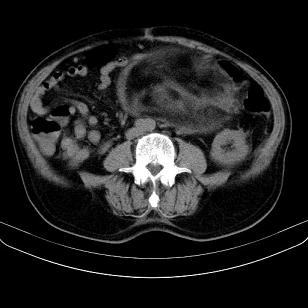

标题: CT21671:男,88岁,左上腹包块 [打印本页]

标题: CT21671:男,88岁,左上腹包块

患者因咳嗽而住院,自觉右上腹包块,无其他不适。

腹膜后高分化脂肪肉瘤

腹膜后脂肪肉瘤

腹膜生占位性病变,脂肪肉瘤可能。

脂肪肉瘤,应测ct值。

支持;后腹膜脂肪肉瘤诊断。

另肠腔扩张及液平,肠梗阻?

左侧腹膜后脂肪肉瘤。